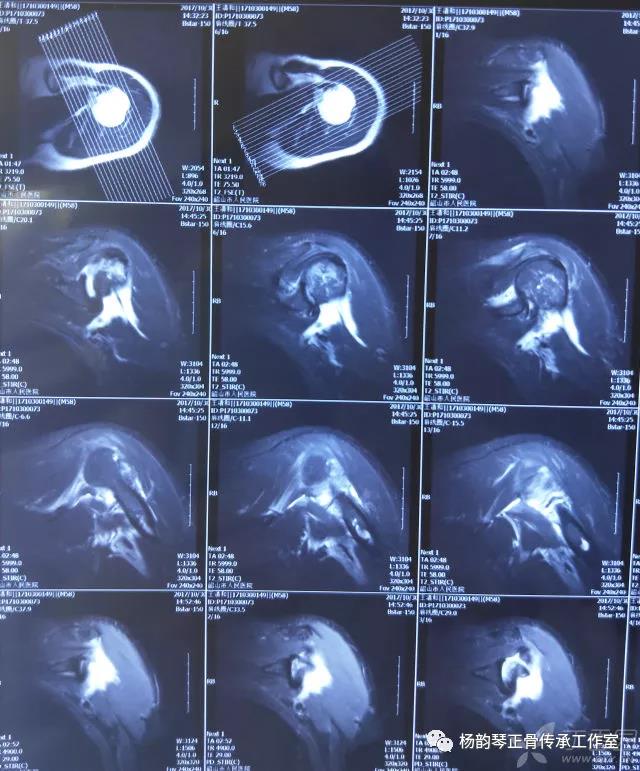

就诊我院后完善CT,诊断明确——左肩关节后脱位:

予以手法复位后拍片复查显示“灯泡征”消失,复位成功。讨论:肩关节后脱位在临床较为少见,特别是影像科经验不足很容易漏报,所以我们临床医生一定要自己仔细阅片,同时要结合体查来进行诊断,防止漏诊。肩关节后脱位时体查也有明显特征:肩关节前方明显变平,喙突较平时明显凸起容易触及,而肩关节后方明显丰满,上臂一般处于内旋内收位,无法主动外旋外展。肩关节后脱位的手法复位相对于前脱位的复位来说也比较容易。患者一般可以取坐位,助手自患侧腋下环抱患者稳定患者躯体,术者一手拉患肢上臂稍牵引内旋,一手自后方推顶肱骨头一般可以复位,如果单纯推顶无法复位也可以术者两手握住伤肢缓慢外展并沿肱骨纵轴牵引,然后逐渐外旋上臂即可复位。整复完成后可以把持患肢作肩关节各个方向的小幅度被动活动,防止肩关节粘连,肩关节后脱位的固定方法与肩关节前脱位的固定方法不同,应将患肢置于上臂外展、后伸、外旋位固定,即外展30度、后伸30度和轻度外旋位,用外展支架固定3周后,循序渐进开始肩关节功能康复。